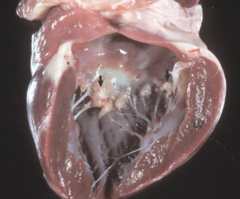

Primary amyloidosis (AL)

-Due to deposition of proteins from Ig Light chains. Can occur as a plasma cell disorder or associated with multiple myeloma. -Often affects multiple organ systems, including renal (nephrotic syndrome), cardiac (restrictive cardiomyopathy, arrhythmia), hematologic (easy bruising, splenomegaly), GI (hepatomegaly), and neurologic (neuropathy).